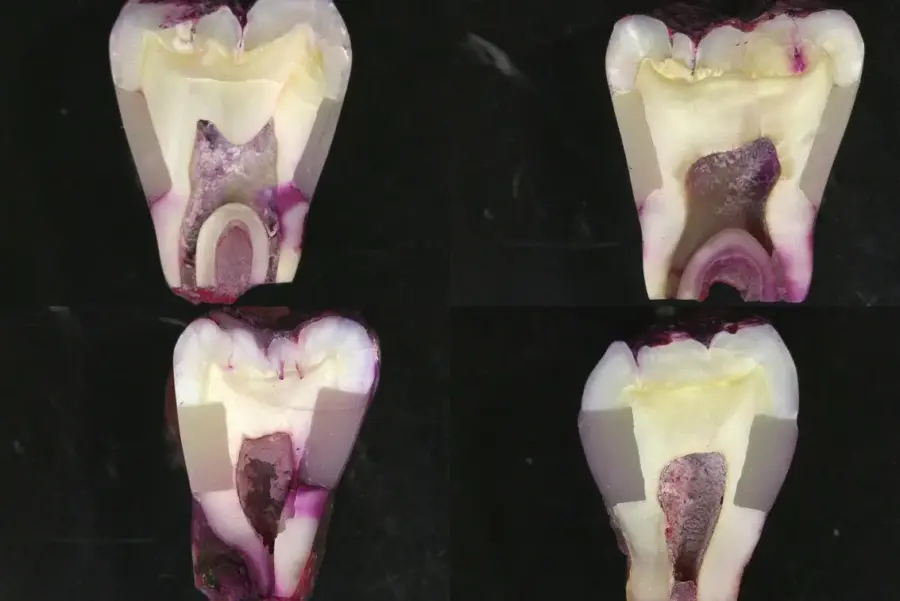

Trong nha khoa hiện đại, vi kẽ trong phục hình cố định được xem là “kẻ thù thầm lặng” làm giảm tuổi thọ của các loại răng sứ, cầu răng hoặc inlay/onlay. Dù phục hình có thẩm mỹ đến đâu, nếu hiện tượng vi kẽ xảy ra, sự hỏng hóc là điều khó tránh khỏi.